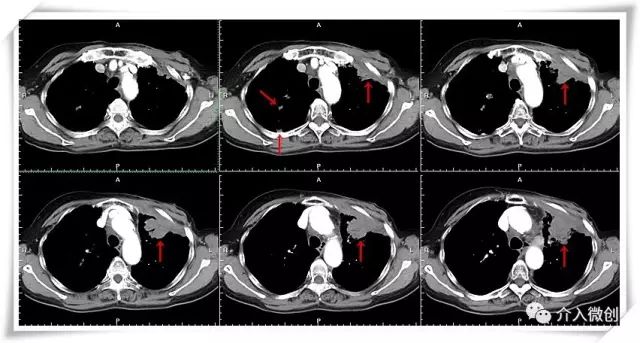

老年女性,双肺、左侧胸壁多发转移瘤,多程传统静脉化疗无效,病灶持续进展。采用多种介入微创治疗技术,多管齐下——CT引导下放射性粒子置入术+支气管动脉化疗栓塞术+支气管动脉化疗灌注术,使得肿瘤病灶得到有效控制。

CT示左侧胸壁肿瘤转移

CT示左肺门肿瘤转移,侵犯、压迫左上肺支气管,累及左肺动脉